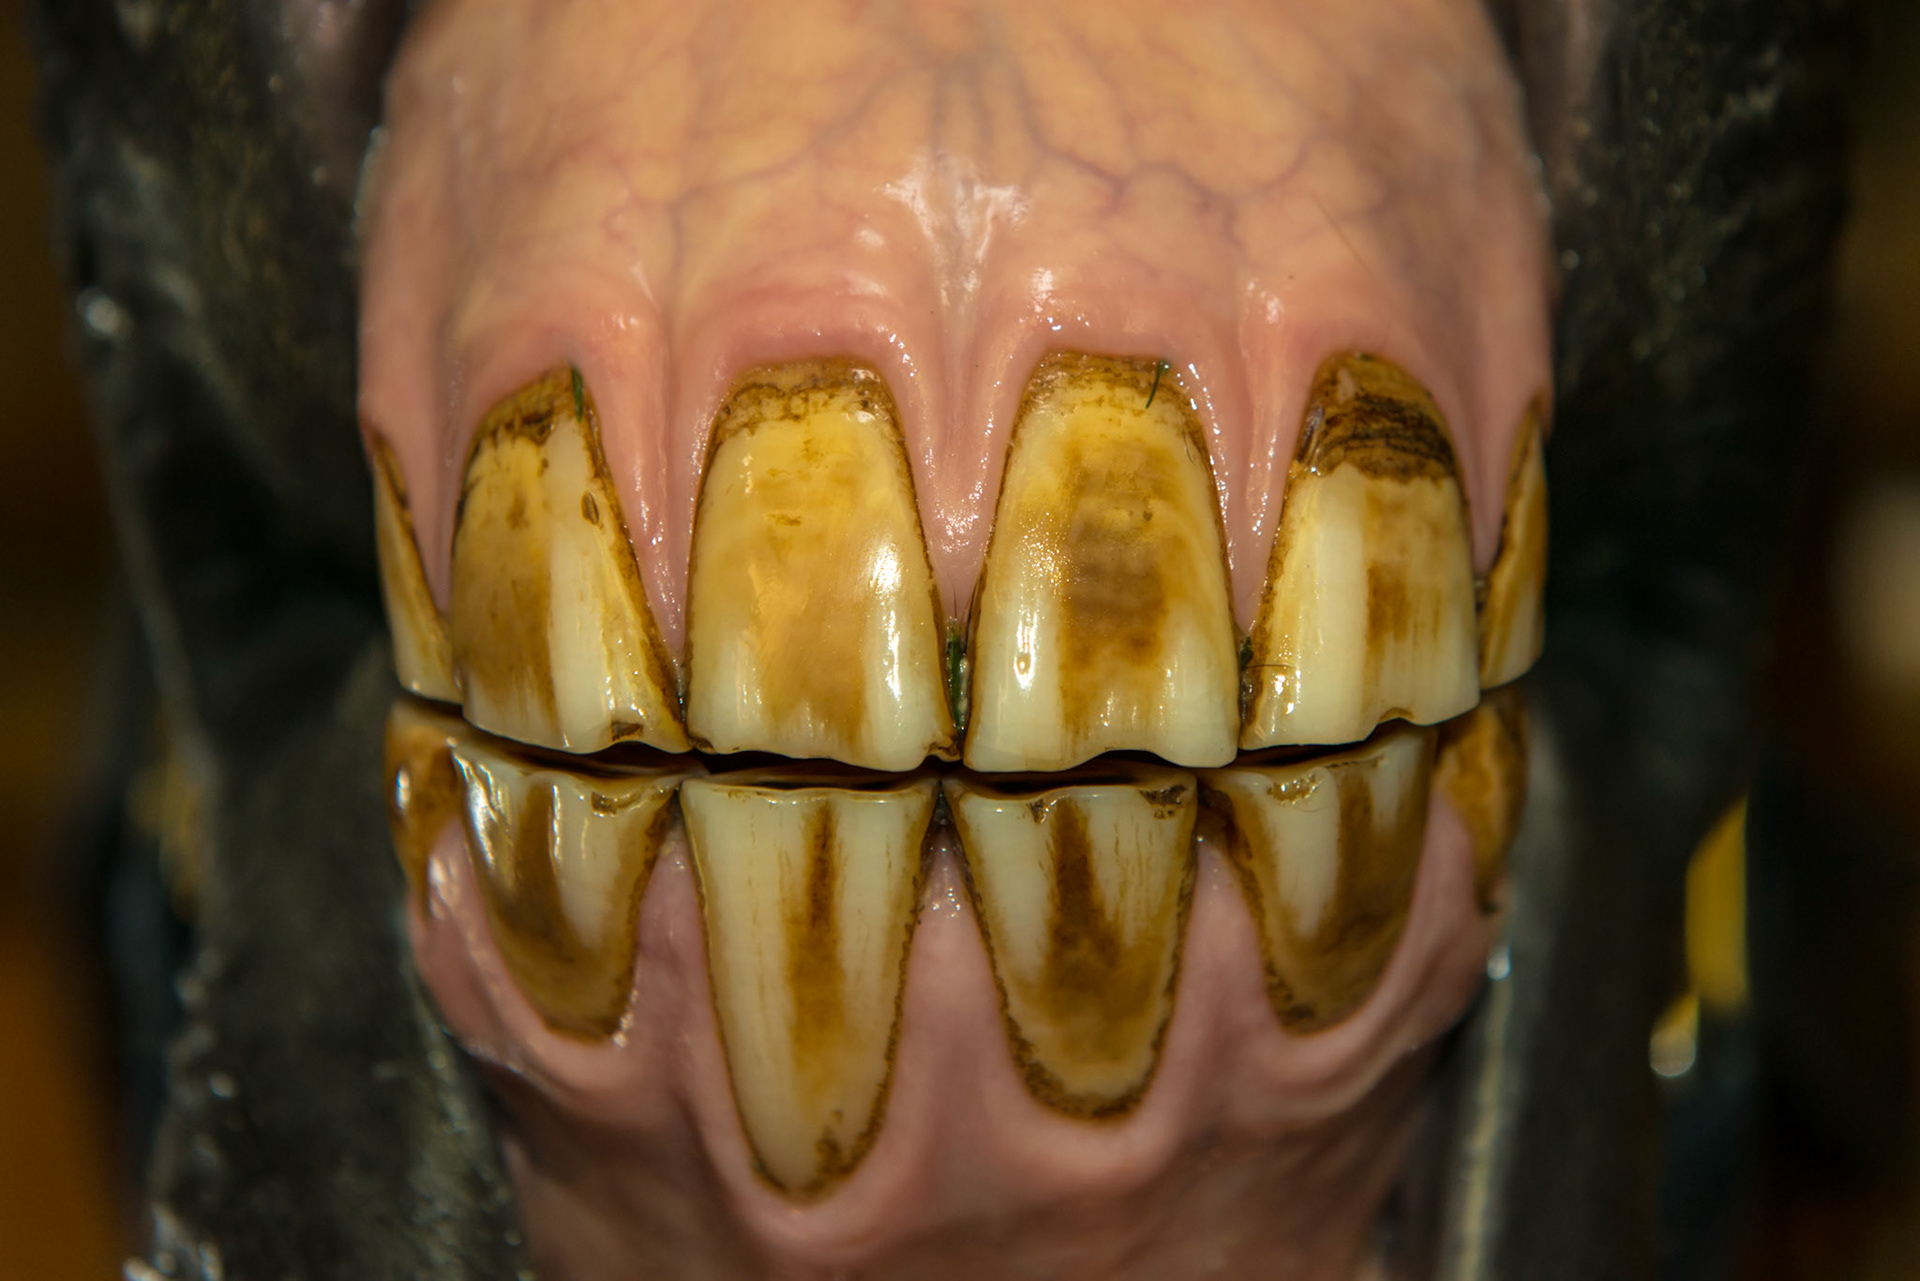

6yr old  Damaged and stained surfaces of all incisors.  Unknown history.